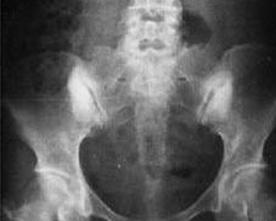

致密性骨发育障碍(condensing osteodysplasty)为常染色体显性遗传性疾病,过去许多学者只认为它是一种侏儒,以后,由于全身性骨骼硬化和锁骨发育不全,Palmar等认为其是骨硬化的一种,或称为锁骨颅骨发育不全。从组织学看来,软骨的超微结构显示软骨细胞内有异常包涵体。